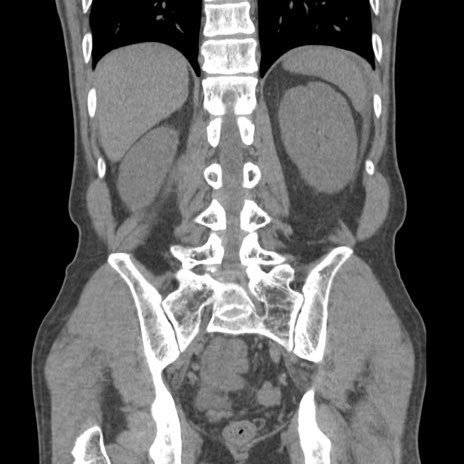

症例56 CT(冠状断像)

脂肪ウインドウ